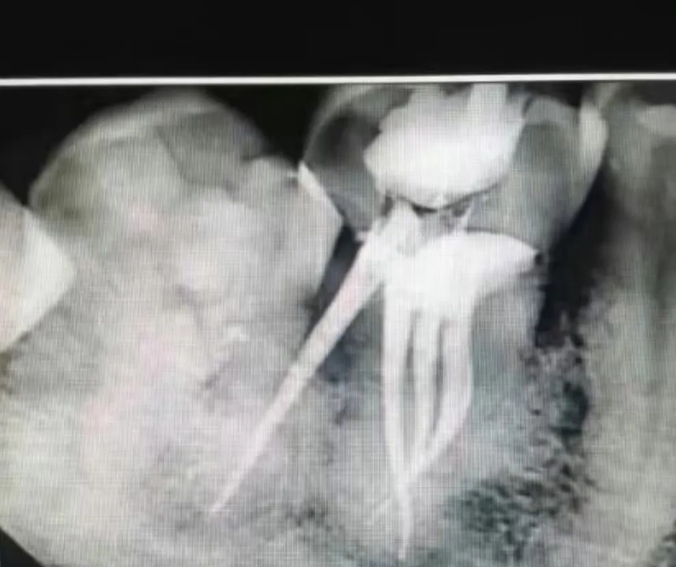

🔎根管治疗

△白色充填物充满整个牙根。